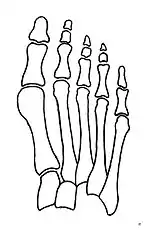

Normal foot skeleton

Fig 1a: Normal foot skeleton

Primus varus deformity is the leaning of the first metatarsal bone away from the second metatarsal and towards the opposite foot (Fig. 1). As it leans over, its head sticks out to form the bunion bump and it also widens the forefoot to cause shoes feeling too tight. Thus when bunion pain becomes unmanageable, surgical correction is to narrow the forefoot by repositioning of the first metatarsal head back to its normal position. This can be done by osteotomy (bone-breaking), soft tissue (non-osteotomy) or fusion techniques.